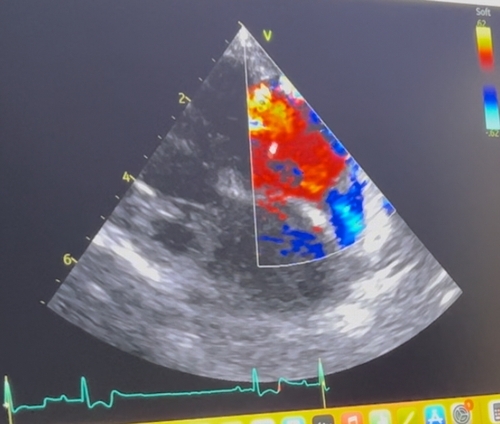

三尖弁閉鎖不全症

心臓の右心房と右心室の間にある三尖弁が正常に閉じなくなり、血液が逆流する病気です。

これにより、心臓に負担がかかり、呼吸困難や咳などの症状が現れます。

アポは僧帽弁閉鎖不全症の手術前の検査で

三尖弁閉鎖不全症による血液の逆流が、多少あることがわかりました。

僧帽弁の手術のおかげで僧帽弁の逆流はほぼなくなったのですが、

今度は三尖弁の負担が増えたことによって、三尖弁側の逆流が増えてしまったそうです。